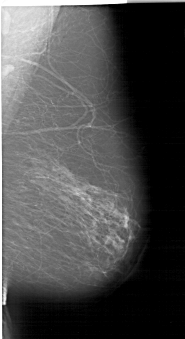

A_1192_1.LEFT_MLO

LEFT_MLO LINES 6856 PIXELS_PER_LINE 3856 BITS_PER_PIXEL 12 RESOLUTION 43.5 OVERLAY

FILE: A_1192_1.LEFT_MLO.OVERLAY

TOTAL_ABNORMALITIES 1

ABNORMALITY 1

LESION_TYPE CALCIFICATION TYPE FINE_LINEAR_BRANCHING DISTRIBUTION LINEAR

ASSESSMENT 4

SUBTLETY 2

PATHOLOGY MALIGNANT

TOTAL_OUTLINES 1

BOUNDARY